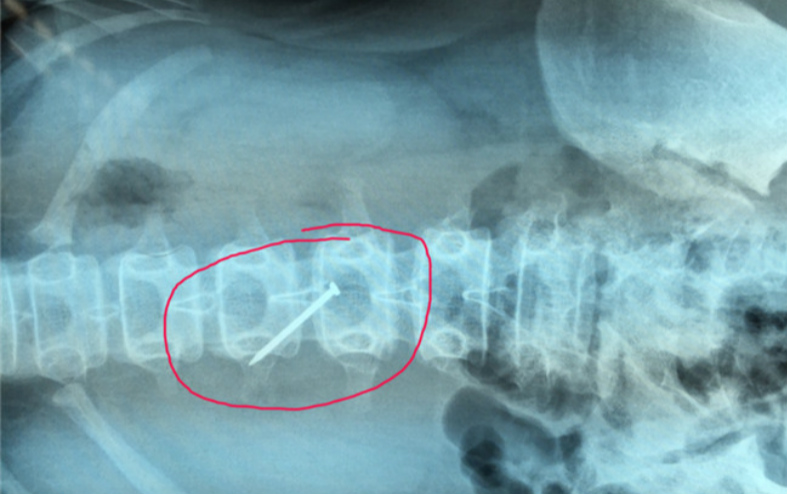

【江苏】女孩胃里发现4厘米铁钉 疑遭同学欺负被逼吞下

一根长近4厘米的铁钉在胃里会怎么样?据《扬子晚报》报道,11月27日晚,江苏泗阳县13岁寄宿学生小轩(化名)在学校“误服”铁钉,其父母到场后了解到,女儿实际是因在学校被同学欺负,而逼迫吞下铁钉。辗转求医之后,这根长近4厘米的铁钉终于在29日下午被取出,这根铁钉当时已刺破小轩胃壁。目前小轩生命体征平稳,处于恢复阶段。此外,小轩父母已向泗阳当地警方报警,目前他们正在查找铁钉来源。

点评:近年来,校园暴力事件被媒体频频曝光。仅在去年,媒体报道的具有一定社会影响的校园暴力事件就有近百起,其中以发生在未成年学生之间的暴力行为居多。教育部等多部门也联合出台意见强调,必须坚决依法惩处校园欺凌事件。然而对于这样的校园悲剧而言,更好地防范才是关键。